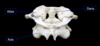

vertebral details

components of vertebral arch

- laminae

- pedicles

intervertebral foramen

The space between the superior articular process and the body is the superior vertebral notch, whereas the space between the inferior articular process and the body is the inferior vertebral notch. A pair of superior and inferior vertebral notches together form an intervertebral foramen, which is a lateral opening from the vertebral canal through which a spinal nerve is transmitted.

vertebral foramen